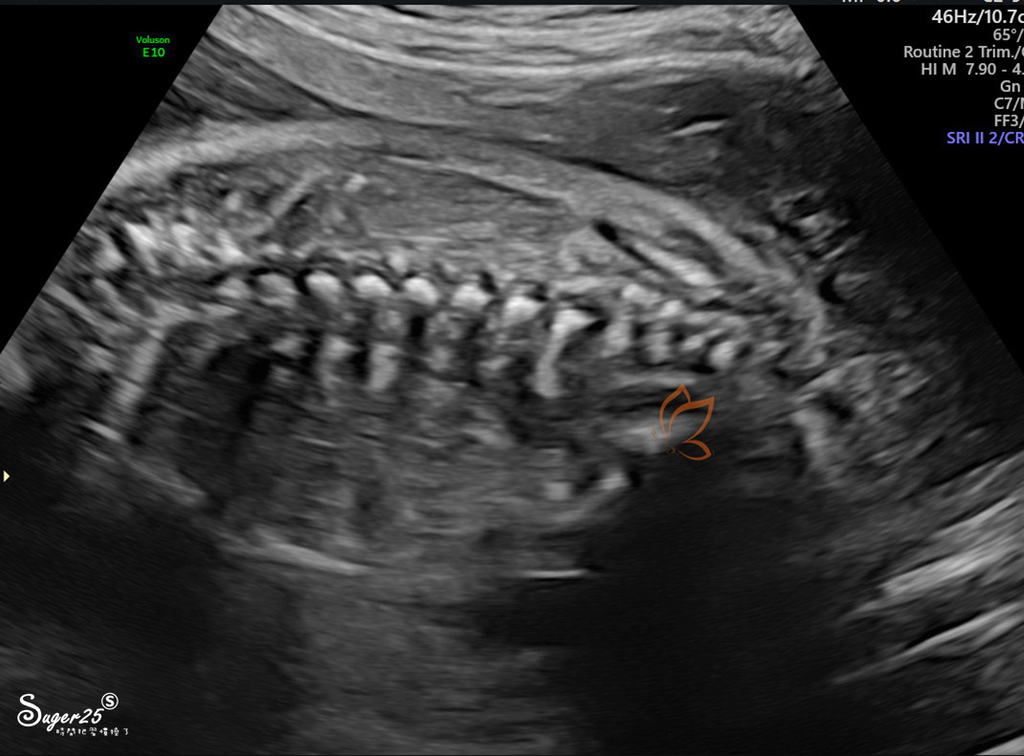

脊髓